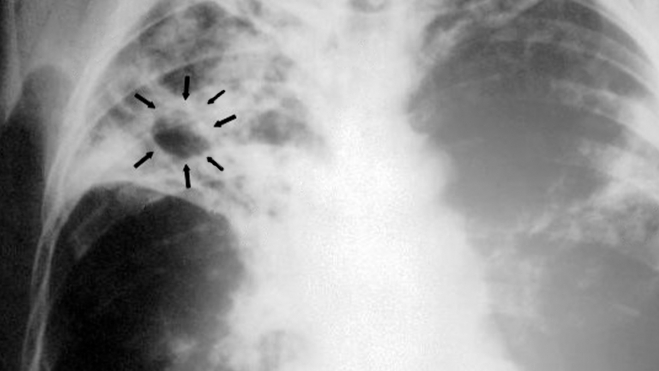

Por tercer año consecutivo, los países de la Unión Europea y el Espacio Económico Europeo (UE/EEE) han registrado un aumento de los diagnósticos de tuberculosis en menores de 15 años. Los nuevos datos publicados por el Centro Europeo para la Prevención y el Control de las Enfermedades (ECDC, por sus siglas en inglés) y la Oficina Regional para Europa de la Organización Mundial de la Salud (OMS) muestran que, con casi 39 000 casos de tuberculosis notificados en 2023, los 29 países de la Unión Europea y del Espacio Económico Europeo siguen registrando aumentos en las notificaciones de tuberculosis. Dado que los niños pequeños tienen un mayor riesgo de desarrollar la enfermedad tuberculosa durante el primer año tras la infección, la tuberculosis infantil sirve como marcador de la transmisión en curso dentro de una comunidad.

Los nuevos datos para 2023 indican que los niños y adolescentes menores de 15 años representaron el 4,3% de todos los casos de tuberculosis en la UE/EEE. Y los casos notificados en este grupo de edad han aumentado, aunque solo sea ligeramente, por tercer año consecutivo. Entre 2022 y 2023, las notificaciones de tuberculosis pediátrica aumentaron de 1 341 a 1 689 casos. Además, para uno de cada cinco niños con tuberculosis en la región se desconoce si completaron su tratamiento antituberculoso. Un tratamiento incompleto puede provocar un deterioro de la salud, como la aparición de tuberculosis farmacorresistente y una mayor transmisión de la enfermedad a otras personas.